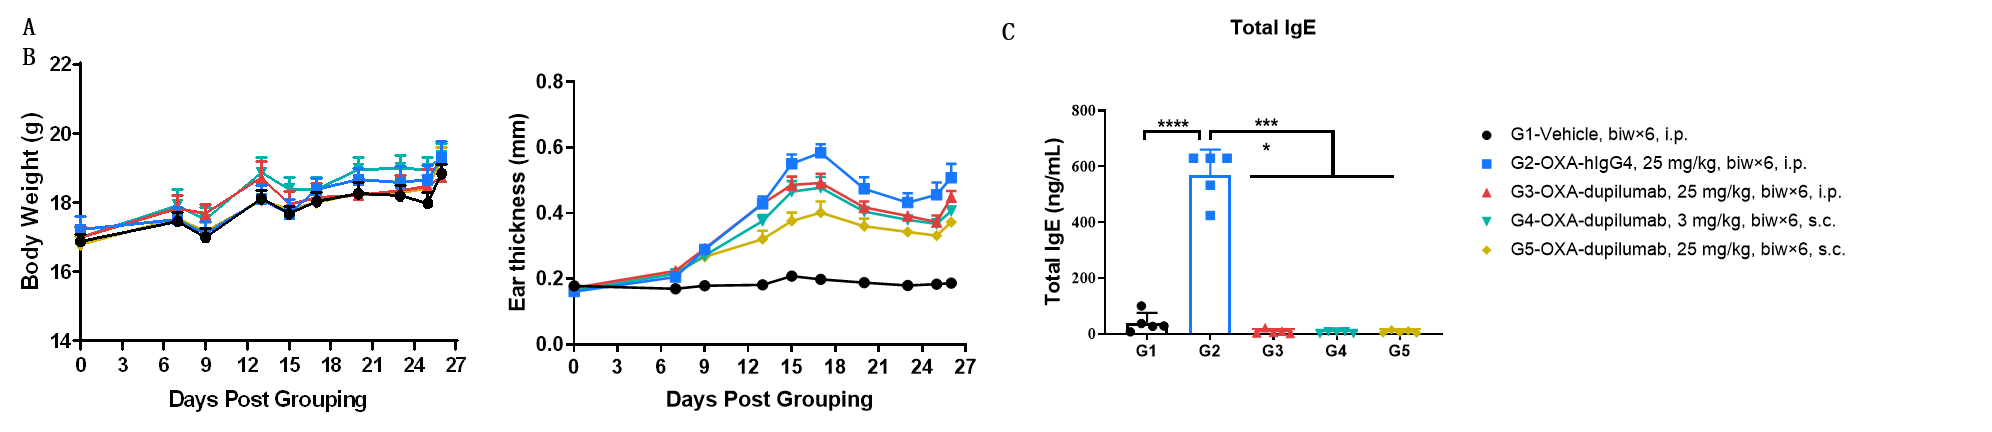

Efficacy of anti-human IL4RA antibody in B-hIL4/hIL4RA mice. Mice in each group were treated with dupilumab (in house) produced in house. Doses are shown in legend. (A) Body weight changes during treatment. (B) Statistical analysis of ear thickness in each group. Epidermis of ear began to desquamate from day 18. So the ear thickness was decreased from day 18 as shown in figure. (C) Total IgE levels in serum. Total IgE levels were measured by ELISA on day 26. Ear thickness and concentrations of total serum IgE were negative related with the doses of antibody. (n = 5).